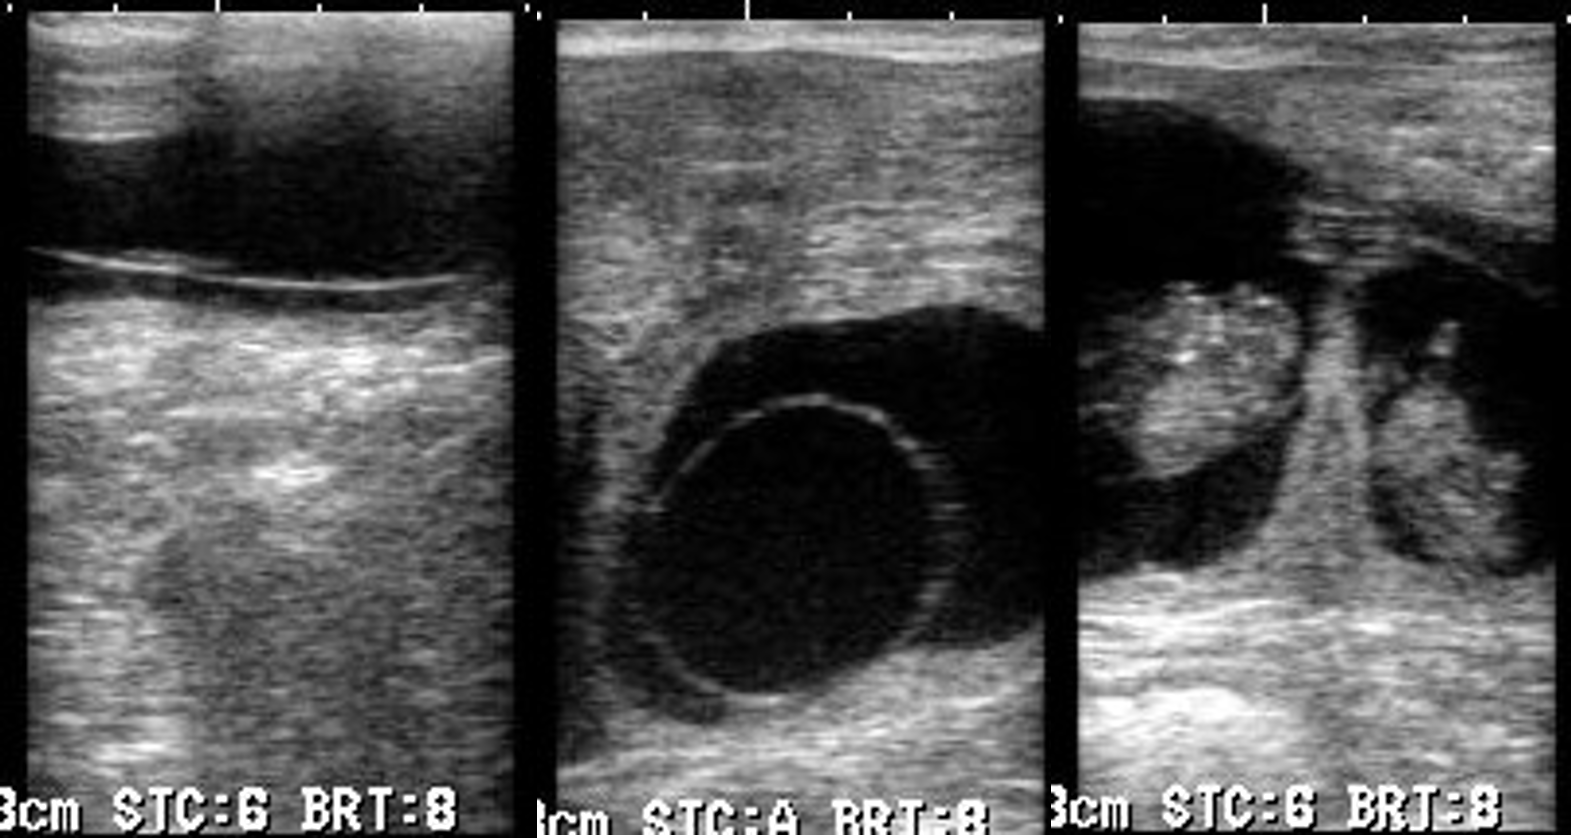

●妊娠鑑定

授精後可能な限り早く(授精後26日より超音波検査を実施)妊娠鑑定ならびに双胎妊娠診断,早期胚芽死滅(EED)を摘発し、繁殖リスクを最小限に留めます。

双胎妊娠